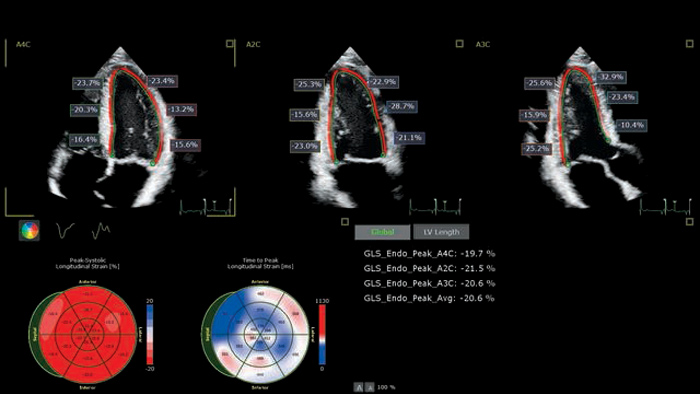

Cardiac imaging modalities support a more confident stratification of cardiovascular toxicity while serving as a powerful baseline reference for treatment and long-term follow-up.

To read the complete 2022 ESC guidelines for cardio-oncology visit our cardiotoxicity page.